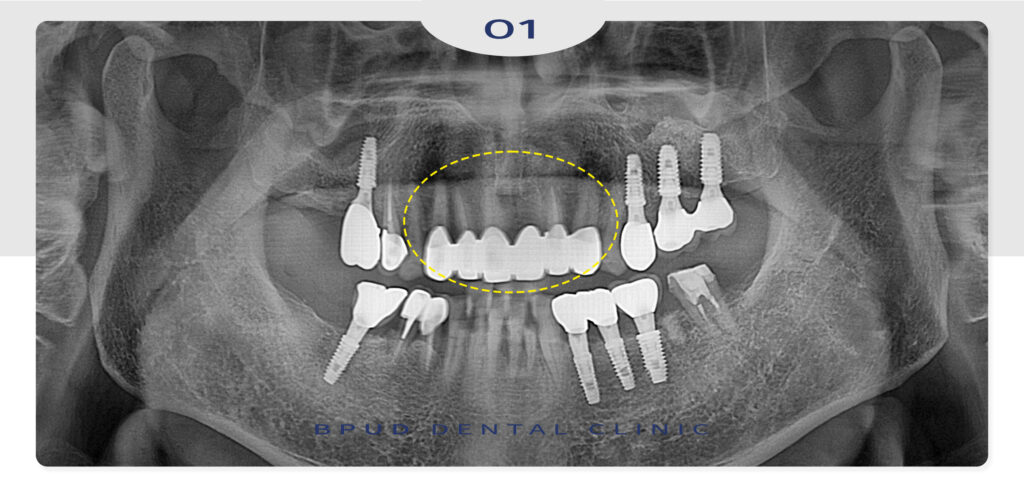

기존에 까맣게 보기가 좋지 않았던 치아들이

심미적으로 바뀌고 난 뒤 자신감도 생기고

환자분께서도 매우 만족하셨는데요.

위쪽 앞니를 하고 나니 너무 예쁘고 좋으셔서

아래쪽 앞니도 진행하실 예정입니다!